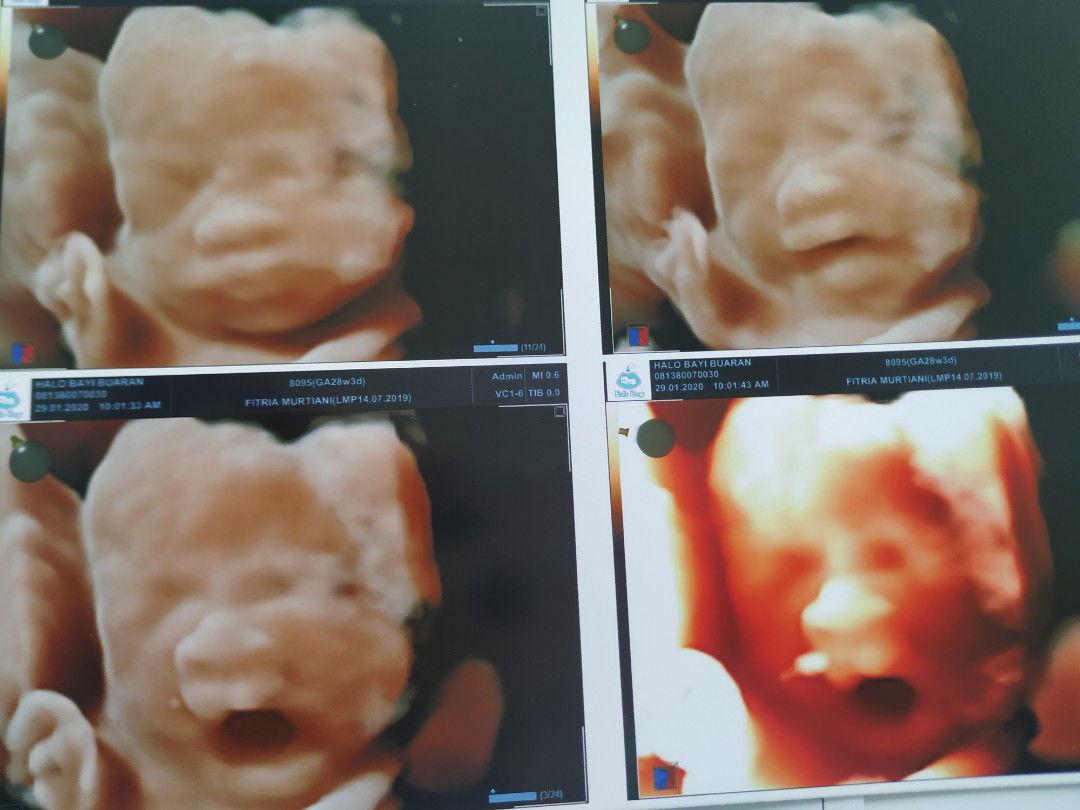

Pertama Kali USG 4D

Alhamdulillah, usia kandungn 28 minggu lebih 3 hari dan hari ini pertama kalinya USG 4D di HaloBayi Buaran. ya Allah alhamdulillah semua sehat, lengkap dan normal.. pertama kali ngeliat mukanya mashaa allah, uda jatuh cinta banged.. sehat terus anak ku sayang, u're the best gift i ever had ❤️ **ngantuk ya nguap terus haha kayak bapaknya nih, idung apalagi ?